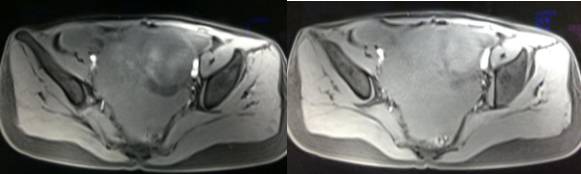

MR检查:

病理结果:黄体血肿

根据时间不同MR信号也有所不同,TIWI脂肪抑制序列可以鉴别脂肪和出血。

卵巢囊肿:呈均匀的T1WI 低信号,T2WI 高信号,边界清楚,壁薄,大多数病灶直径≤5 cm,但囊肿的起源及定性诊断困难。

功能性囊肿:因囊肿内容物成分不同,信号可有改变,随访观察数月后其信号和大小可出现变化或消失。

巧克力囊肿:常呈多发的单囊或多囊改变,病灶大小不等,囊壁厚薄不均,囊内信号复杂,囊内或各囊腔间血液因出血时期不同,信号常呈多样性,囊肿内反复出血、破裂,形成相互粘连的多房性囊肿,是其较为特征性的表现。

在鉴别卵巢畸胎瘤、出血性囊肿或巧克力囊肿时,MR 脂肪抑制T1WI 可明确肿块内高信号成分是脂肪还是出血,同时由于脂肪组织与非脂肪组织的共振频率不同,在两者交界处沿磁场频率编码方向出现化学位移伪影,但出血性囊肿与巧克力囊肿的鉴别有时较为困难。